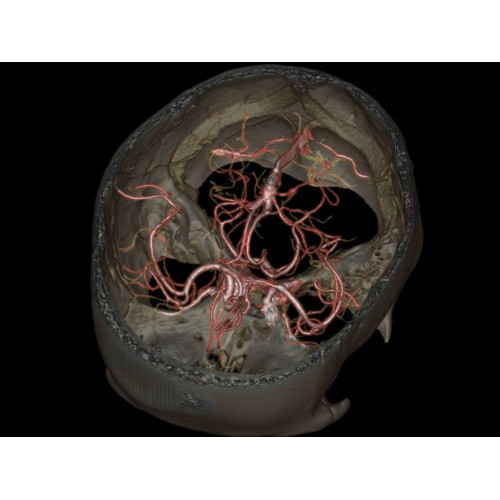

Позволяет проводить комплексные исследования всех анатомических зон, включая нейровизуализацию, ангиографию, исследования органов грудной и брюшной полости. Особенно эффективен для раннего выявления онкологических заболеваний.

Специализированные исследования